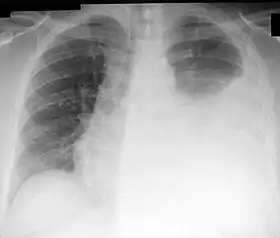

Chest X-ray showing a left-sided pleural effusion (right side of image). This can be treated with thoracentesis.